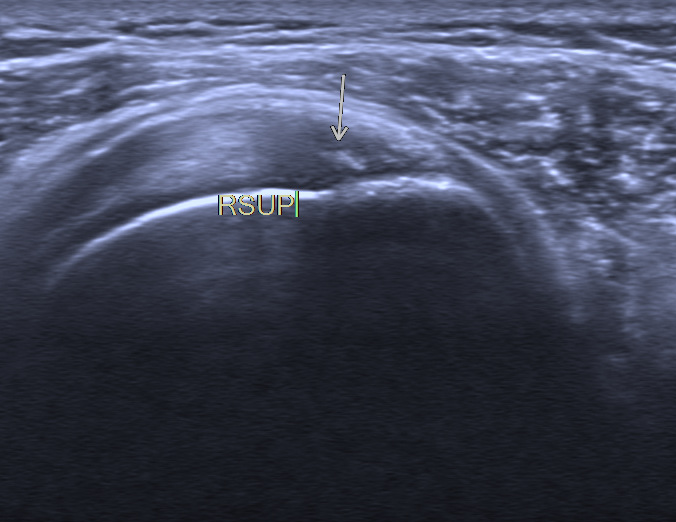

3.肩关节周围滑囊炎

诊断主要依靠测量肩峰下-三角肌下滑囊的厚度,其正常厚度应小于2mm,当滑囊厚度增加超过正常值时,结合临床症状及病史可初步诊断。